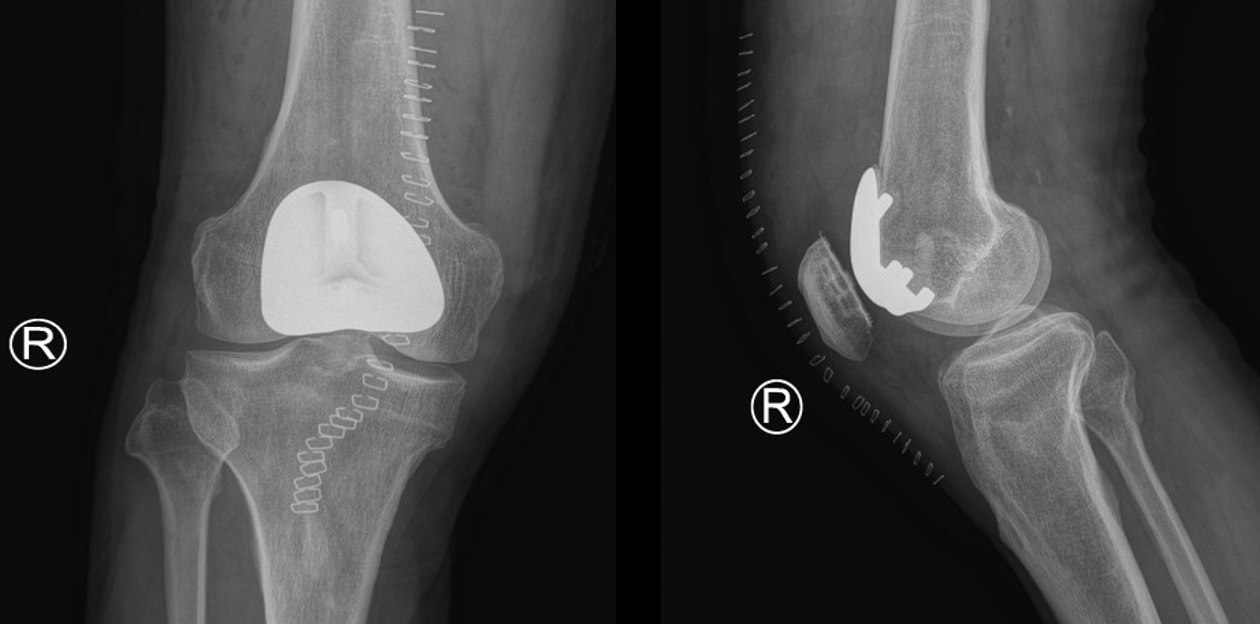

针对王先生的特殊病情,权松涛主诊医师团队与喻长纯主任经过深入的术前讨论,决定为其施行创伤更小、恢复更快的髌股关节置换术。此手术仅置换病变的髌股关节面,能够完整保留膝关节的交叉韧带和内外侧间室,最大程度地保留了膝关节的正常生理功能,是实现快速康复的关键。

术中,膝关节外三科团队在喻长纯主任的指导下精准操作,成功为王先生置换了受损的股骨滑车及髌骨关节面。手术过程顺利,术后患者安返病房。